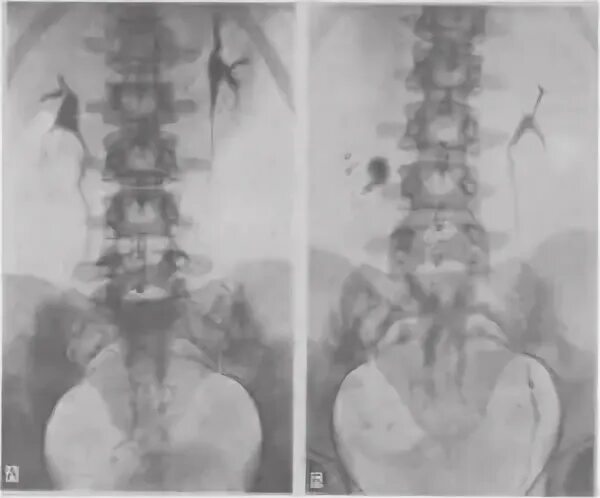

Нефроптоз 2 степени что это